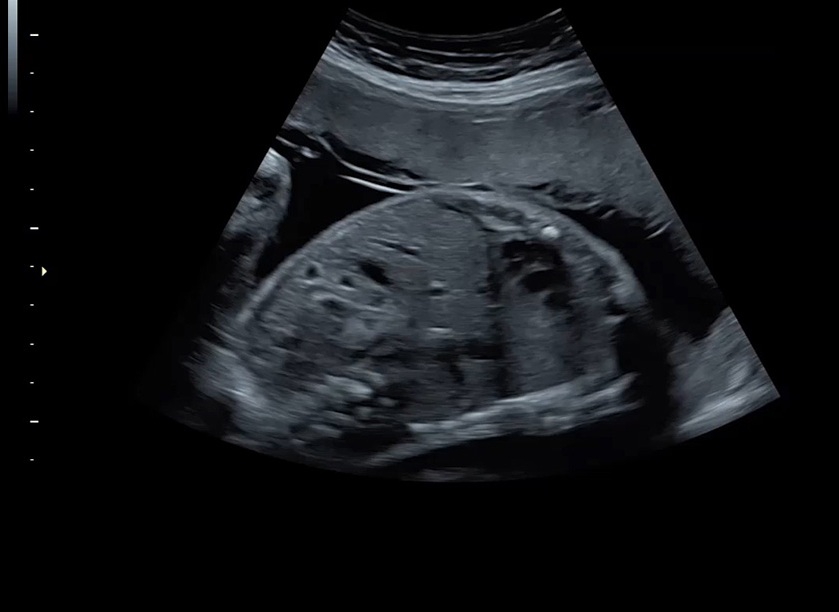

• Высокое качество изображений: Voluson S8 обеспечивает высококачественные изображения, позволяющие детально оценить состояние плода и обнаружить возможные патологии.

• Сложные инструменты для оценки качества плода: Сканер оснащен инновационными инструментами, позволяющими проводить детальную оценку состояния плода, включая его сердечную деятельность, анатомию и кровоток.

• Технология автоматической фетометрии в 2D режиме (SonoBiometry): Эта технология позволяет автоматически измерять бипариетальный размер, окружность головы, окружность живота, длину бедра и плеча плода, обеспечивая точные и надежные измерения.